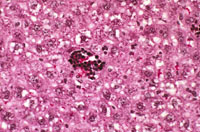

Extramedullary hematopoiesis (EMH) can occur in the liver, especially when there is long-standing anemia. Typical morphological features consist of small aggregates of cells with intensely basophilic nuclei (erythroid) or small collections of immature and mature myelocytic cells (myelopoiesis) located in the sinusoids and, in severe cases, in portal areas.

Extramedullary hematopoiesis characterized by small aggregates of immature erythroid cells.